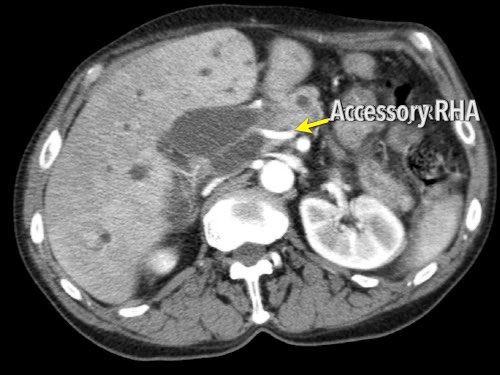

Các hình ảnh mặt phẳng đứng ngang của một bệnh nhân có khối u ở đầu tụy và động mạch gan phải phụ thêm.

Lưu ý sự áp sát của động mạch phụ thêm bởi khối u.